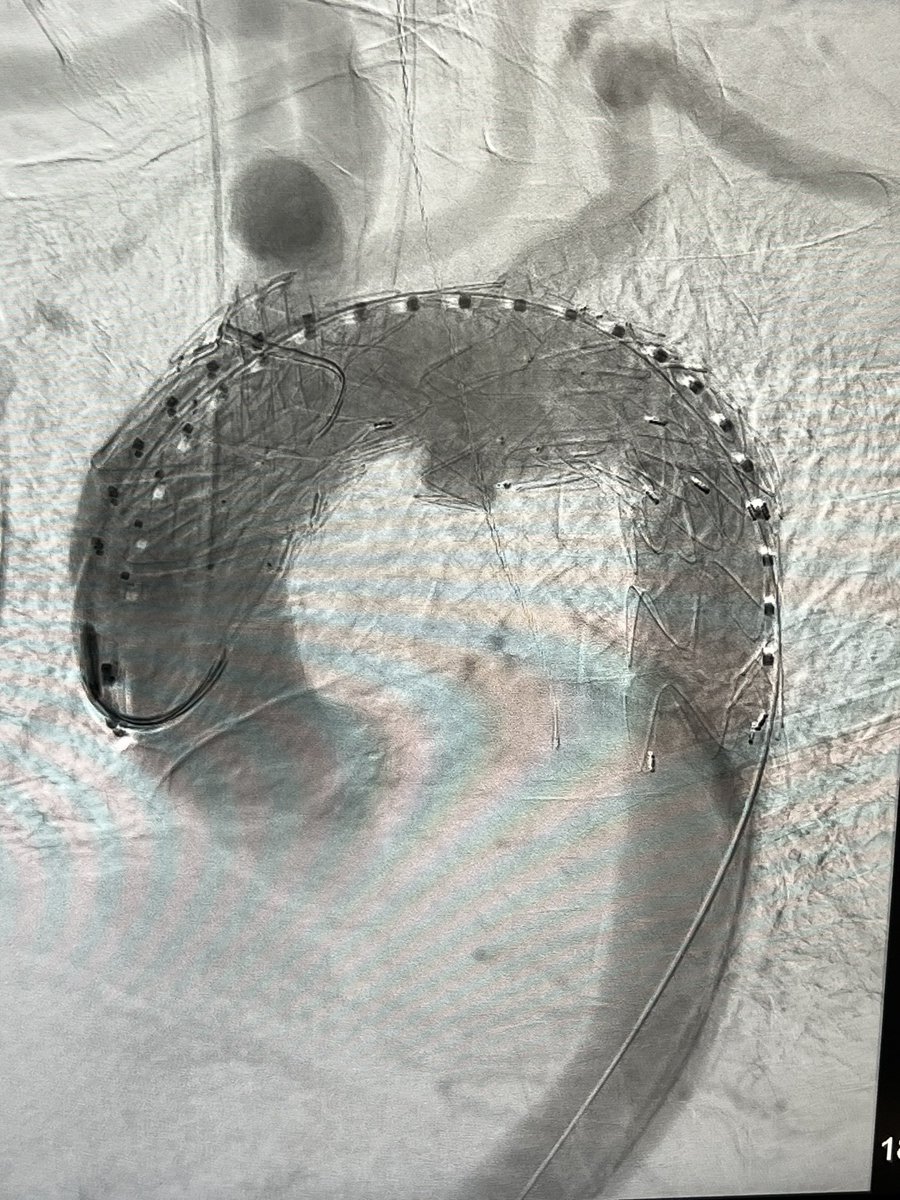

6 pack aorta?! Omentum gone from prior colonic resection after ischemic colitis…referred for an infected ABFB. Bilateral rectus abdominis flaps used to assist in coverage of rifampin soaked graft. @uazphxsurgery